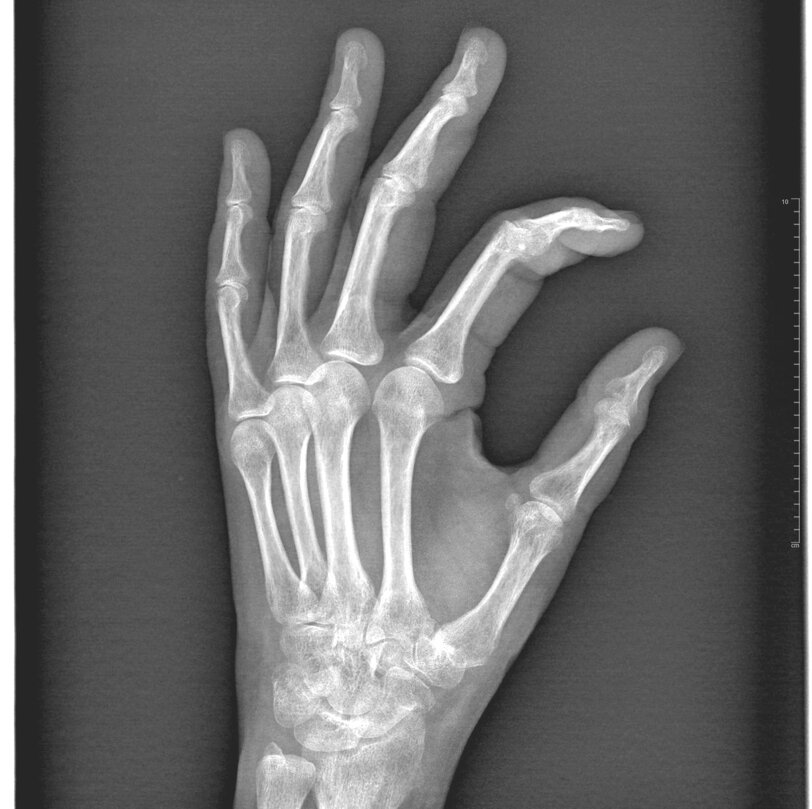

L'indagine diagnostica principale per poter eseguire la diagnosi è la radiografia della mano.

La rizoartrosi è una forma di artrosi che provoca dolore alla base del pollice e difficoltà a pizzicare e afferrare a causa dell'artrosi dell'articolazione trapezio-metacarpale.

Rappresentano la più comune forma di artrosi della mano, evidenziabile nel 25% deigli uomini e nel 40% delle donne con età > 75 anni.

• Stadio I: riduzione dello spazio articolare;

• Stadio II: riduzione dello spazio articolare, con sclerosi ed osteofiti inferiori 2mm

• Stadio III: riduzione dello spazio articolare, con sclerosi ed osteofiti maggiori 2mm

• Stadio IV: artrosi diffusa anche allo spazio scafo-trapezoidale

Clinicamente il paziente presenta dolore alla base del I metacarpo, con difficoltà a mantenere la pinzatura (pressione tra I e II raggio). Il grind test (pressione e movimenti circolari del I metacarpo) evoca dolore e crepitii.